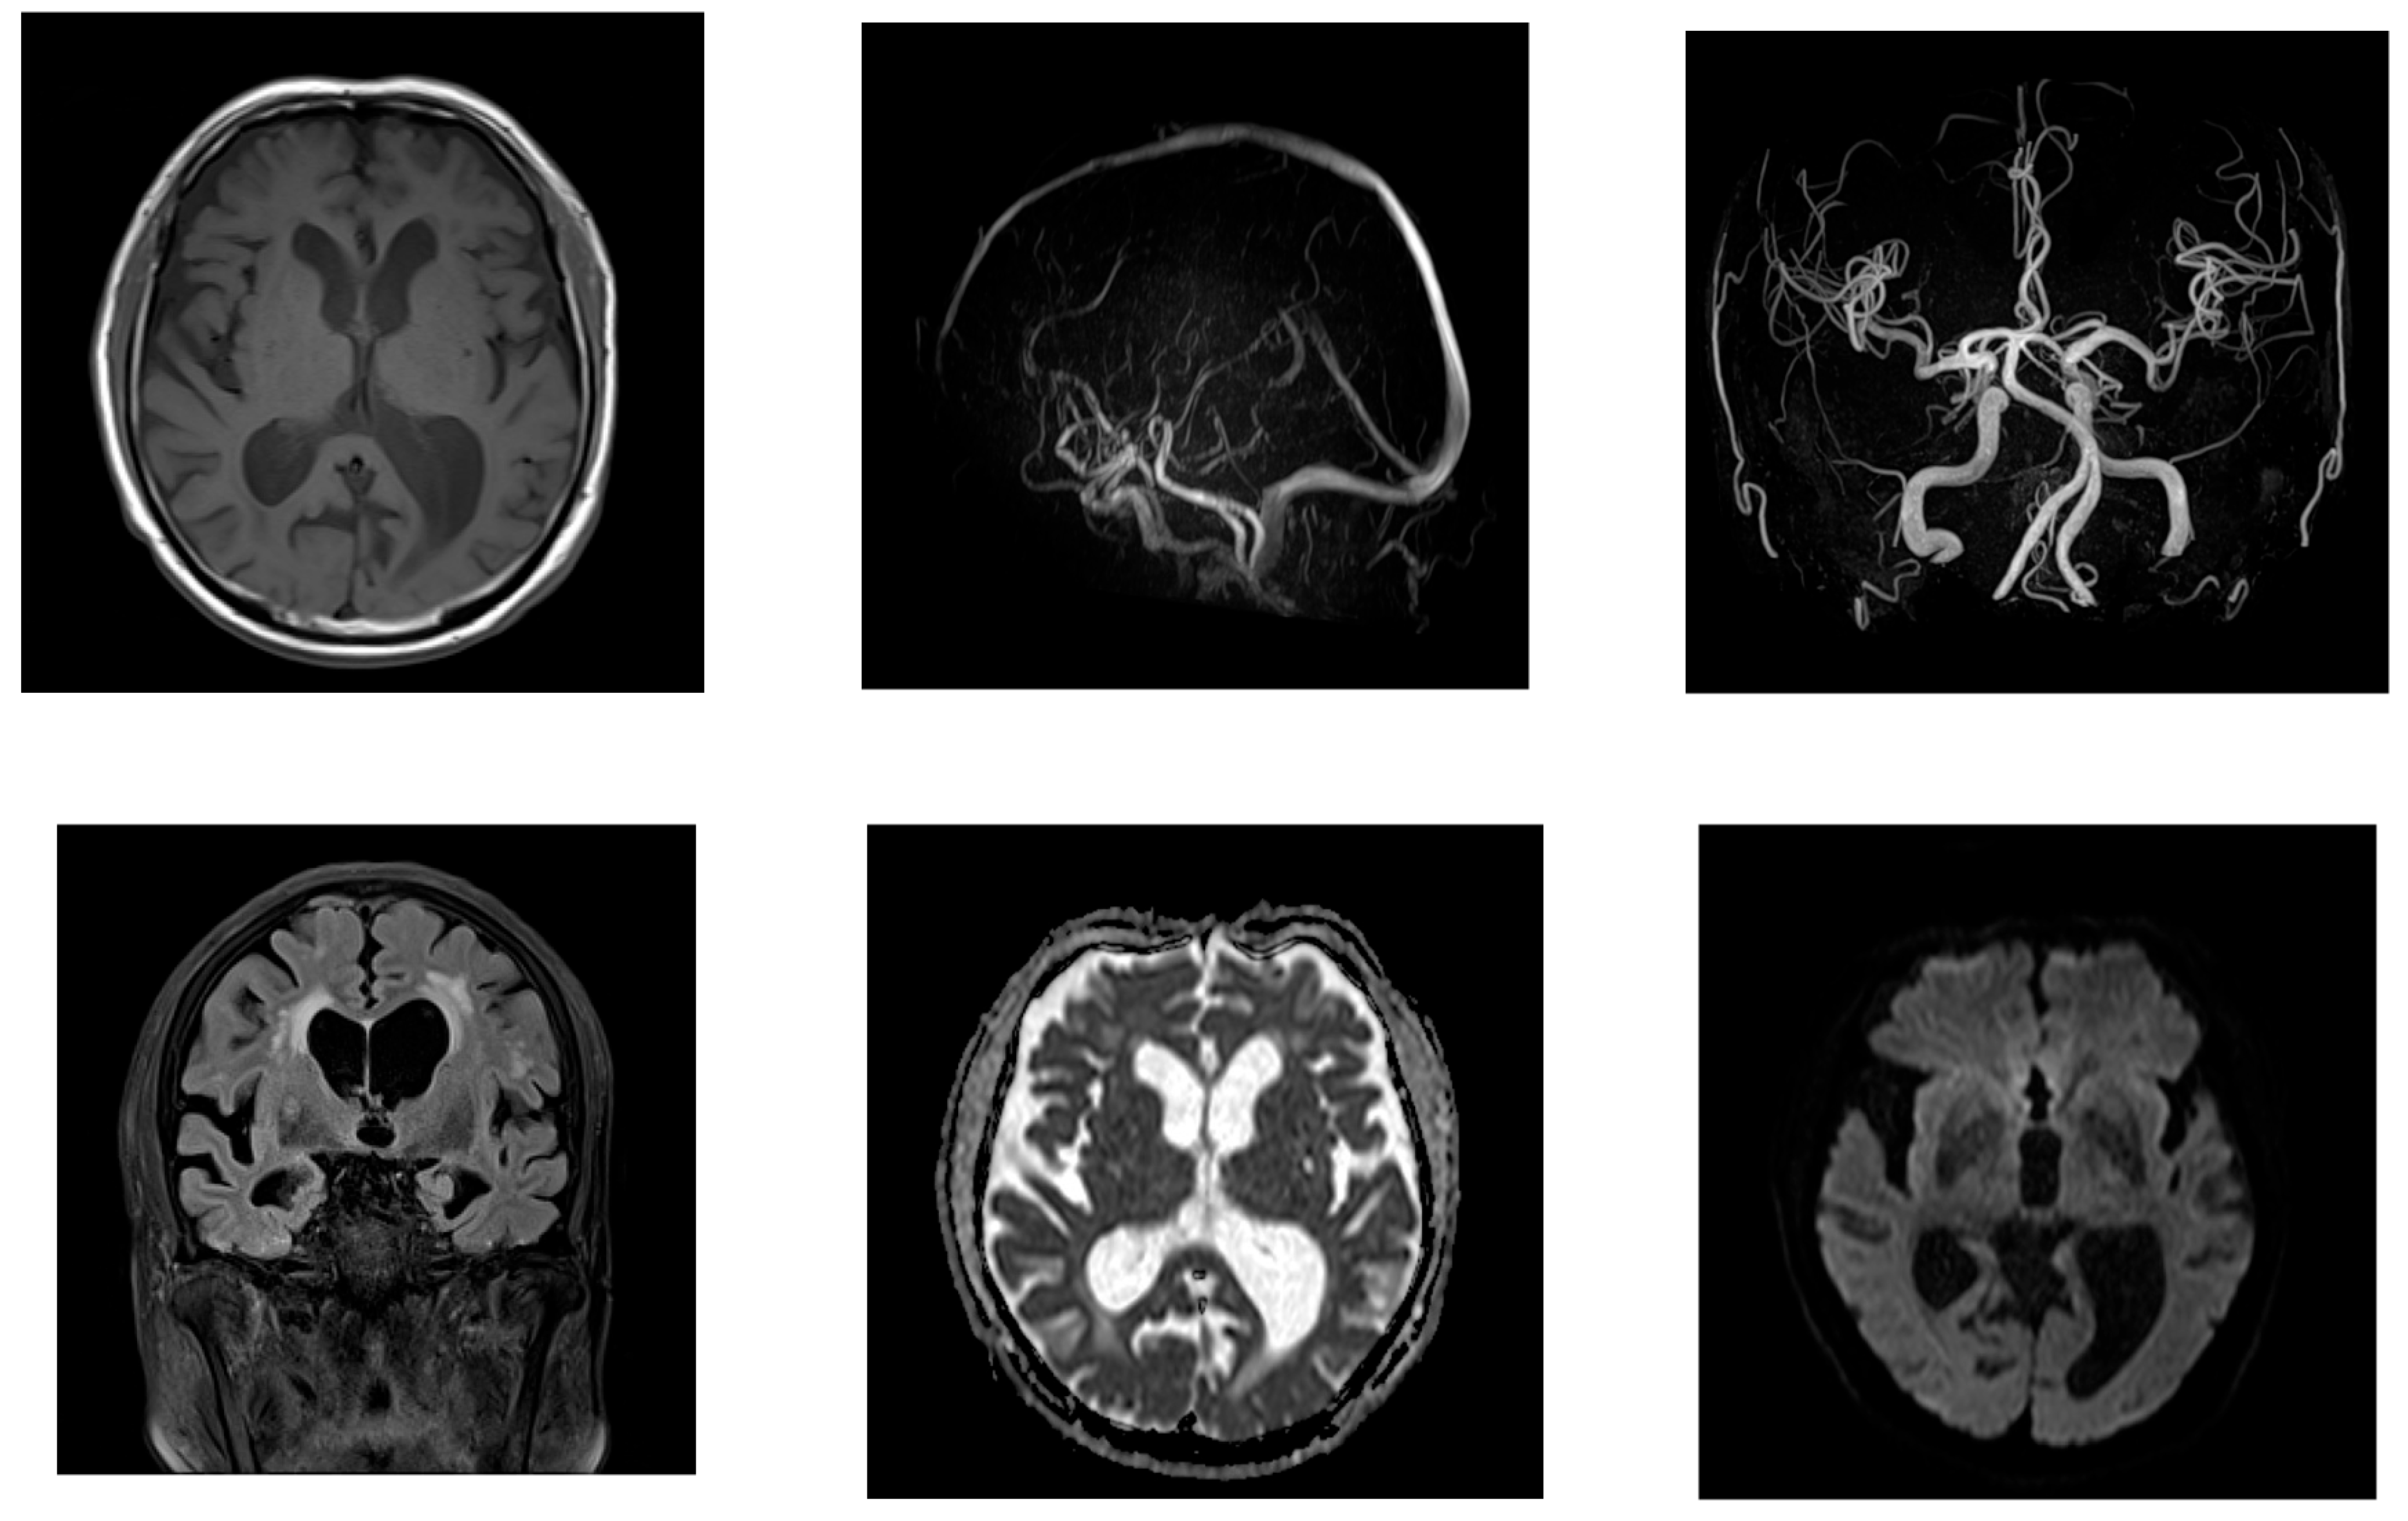

2.1. Case 1